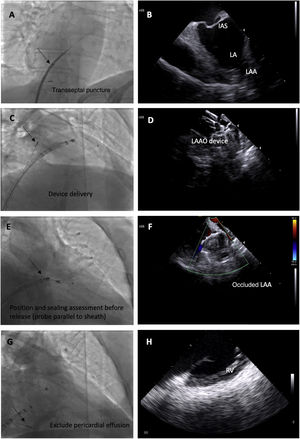

We used the following ICE imaging protocol for LAAO (example images in Figure 3):

The probe is placed in the mid right atrium with clockwise rotation and posterior tilt to better visualize the fossa ovalis and to guide transseptal puncture in an inferoposterior position. In this view, the LAA is visualized in far field to ensure alignment in the anteroposterior plane and direction of puncture toward the LAA.

The transseptal puncture is enlarged with the LAAO device delivery sheath to facilitate the passage of the ICE catheter to the left through the same orifice.

The ICE catheter is placed parallel to the LAO with posterior tilt to guide device delivery. This position is used to guide the LAAO device landing zone with the LAA, assess correct positioning and stability before release, rule out significant peridevice leaks and monitor for possible embolization.

Finally, after LAAO, the probe is retracted to the right side of the heart and is placed in the right ventricle to exclude pericardial effusion.

Fluoroscopic images of the intracardiac echocardiography probe (black arrows) and its respective echographic images during a left atrial appendage (LAA) occlusion (LAAO) procedure, showing its utility in guiding transseptal puncture (A and B); device deployment (C and D); assessment of device position, significant peridevice leaks using color Doppler and embolization risk (E and F) and exclusion of pericardial effusion (G and H). IAS: interatrial septum.